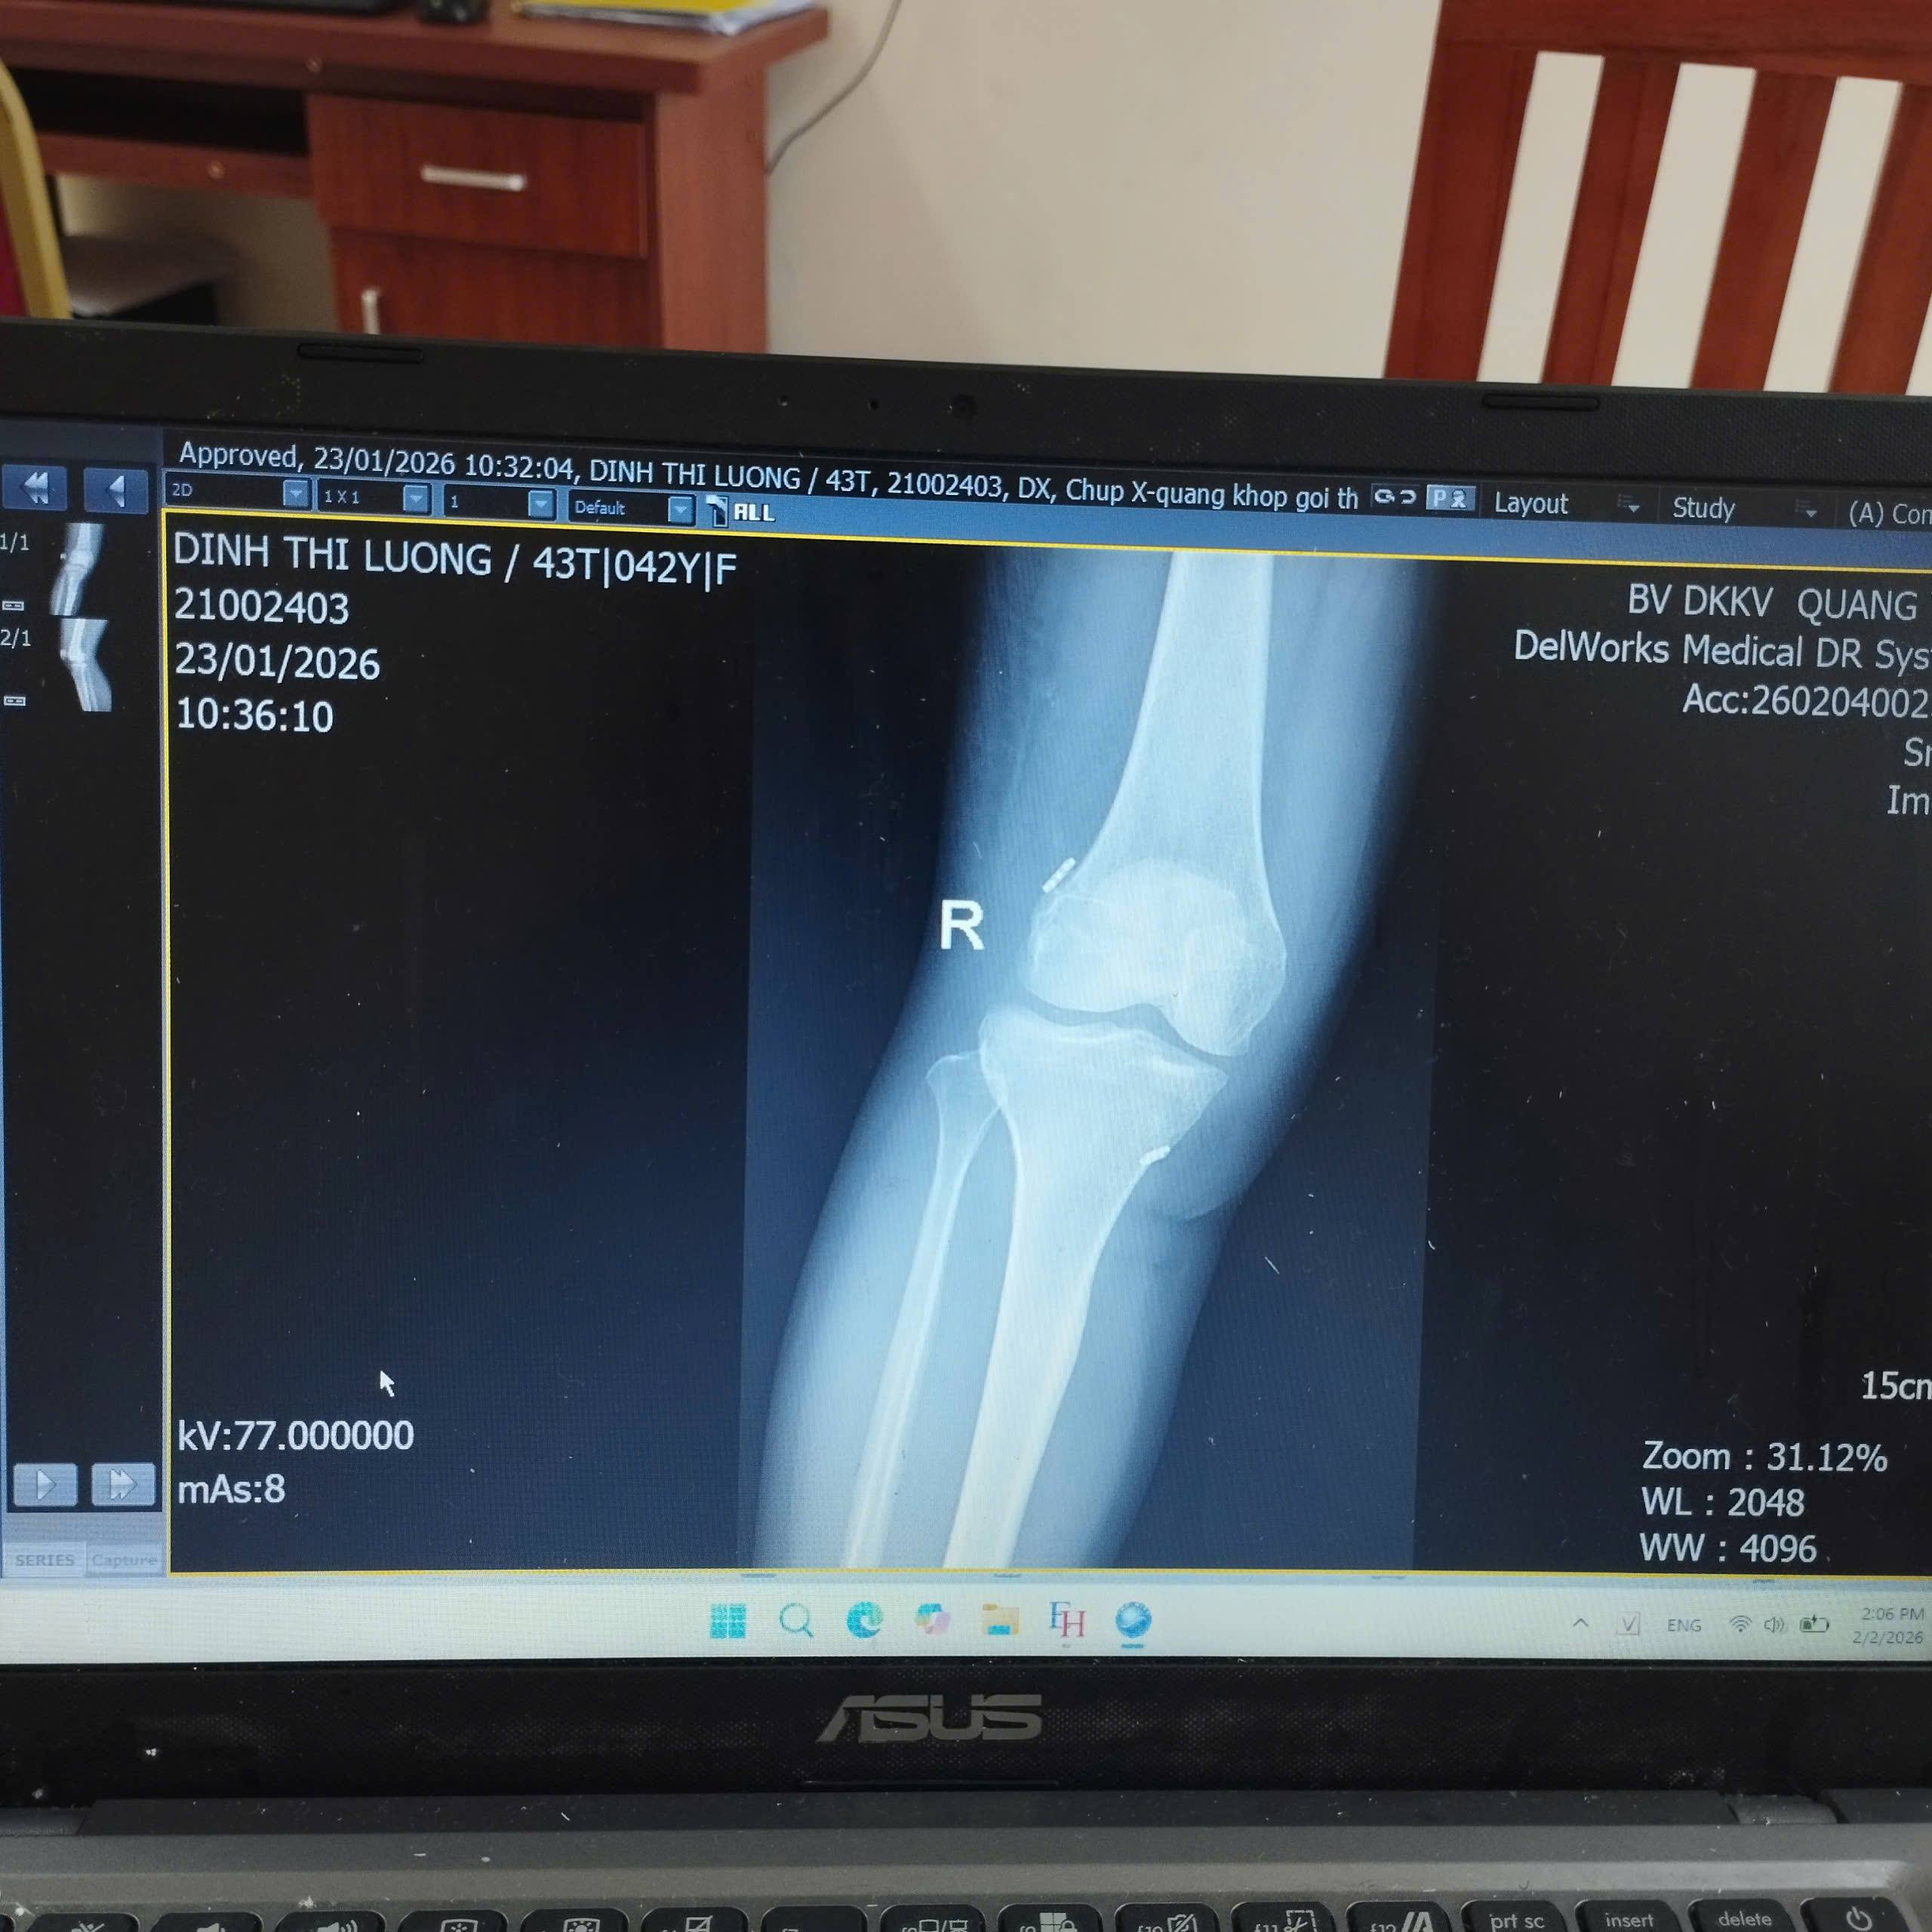

Anh-tin-baiX-quang sau mổ

Qua thăm khám lâm sàng và các xét nghiệm cận lâm sàng, các bác sĩ chẩn đoán bệnh nhân bị chấn thương khớp gối phải, tổn thương sụn chêm và dây chằng chéo trước. Trước tình trạng tổn thương phức tạp, bệnh nhân được chỉ định phẫu thuật nội soi khớp gối cắt sửa sụn chêm và tái tạo dây chằng chéo trước.

Ca phẫu thuật diễn ra thuận lợi, an toàn, các tổn thương được xử lý triệt để, đảm bảo đúng quy trình kỹ thuật. Sau mổ, bệnh nhân tỉnh táo, tình trạng ổn định, giảm đau rõ rệt và đang được tiếp tục theo dõi, chăm sóc, tập phục hồi chức năng theo phác đồ.